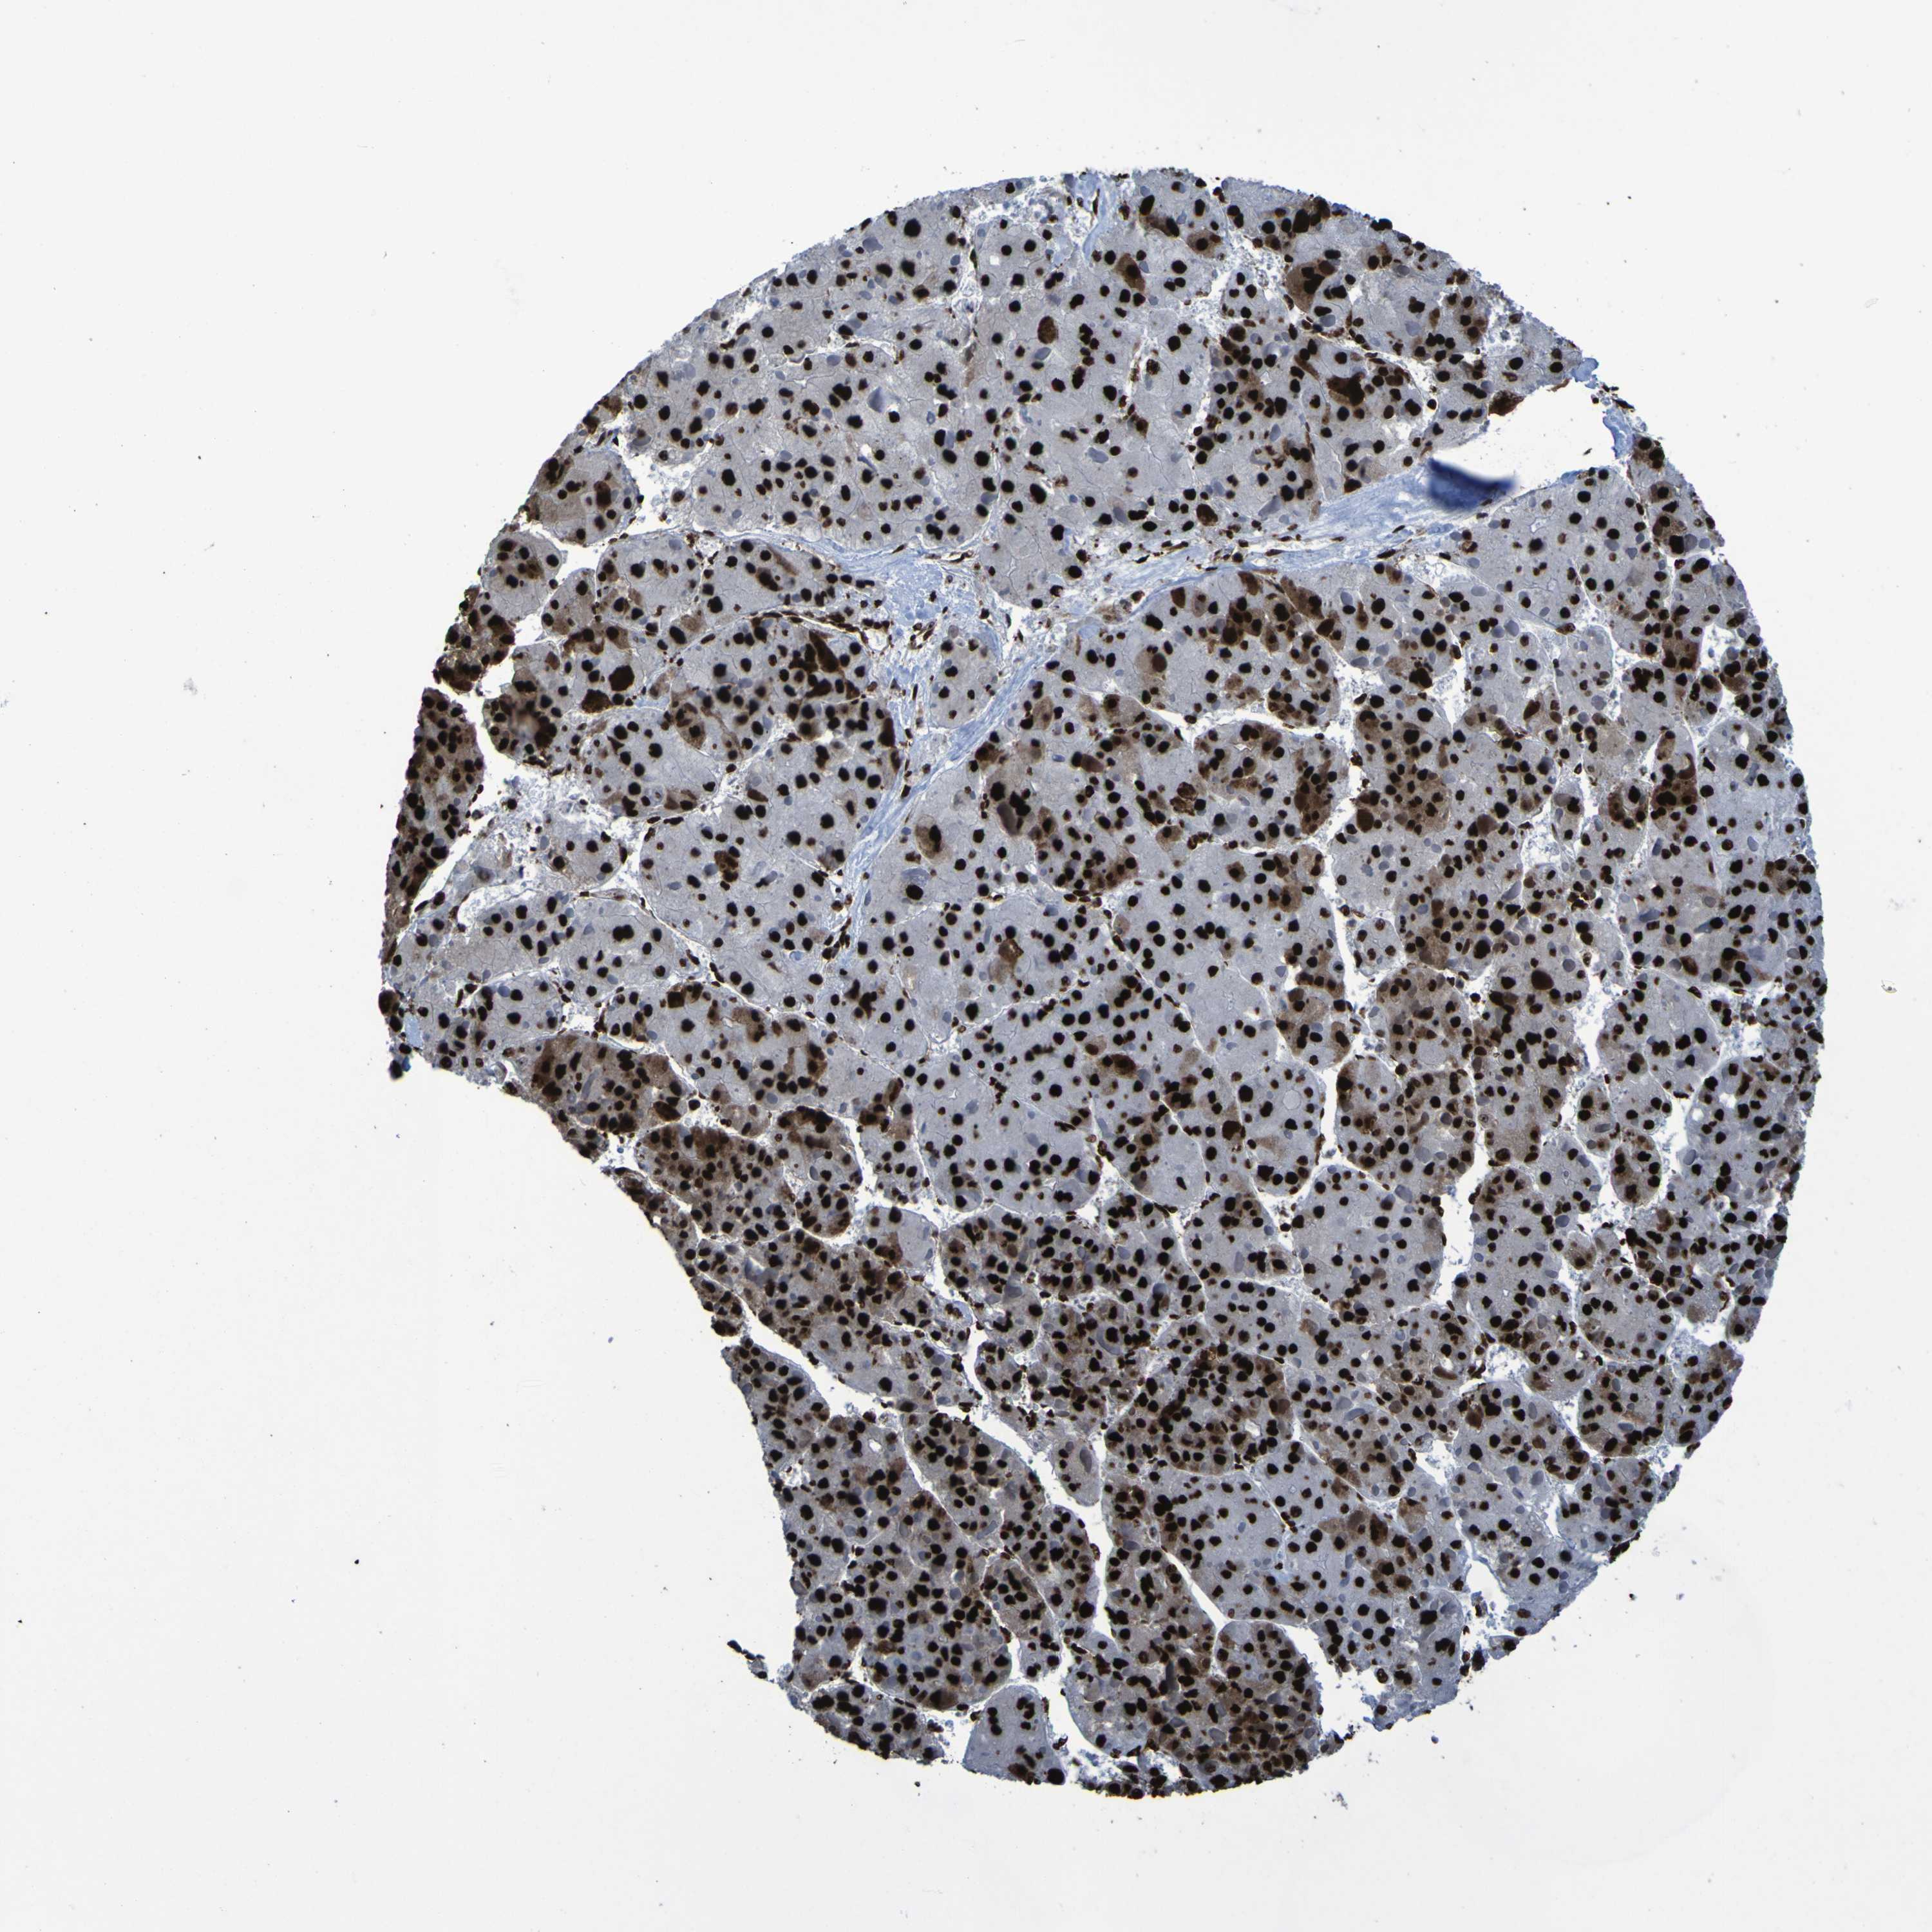

LIVER CANCER - Protein expressioni

A mouse-over function shows sample information and annotation data. Click on an image to view it in a full screen mode. Samples can be filtered based on level of antibody staining by selecting one or several of the following categories: high, medium, low and not detected. The assay and annotation is described here.

Antibody stainingi

Antibody staining in the annotated cell types in the current human tissue is reported as not detected, low, medium, or high, based on conventional immunohistochemistry profiling in selected tissues. This score is based on the combination of the staining intensity and fraction of stained cells.

Each image is clickable and will lead to virtual microscopy that enables deeper exploration of all samples and also displays staining intensity scores, fraction scores and subcellular localization as well as patient and tissue information for each sample.

Antibody HPA011384

Antibody CAB012983

Staining

High

Medium

Low

Not detected

Intensity

Strong

Moderate

Weak

Negative

Quantity

>75%

75%-25%

<25%

None

Location

Nuclear

Cytoplasmic/membranous

Cytoplasmic/membranous,nuclear

Cholangiocarcinoma

Carcinoma, Hepatocellular, NOS